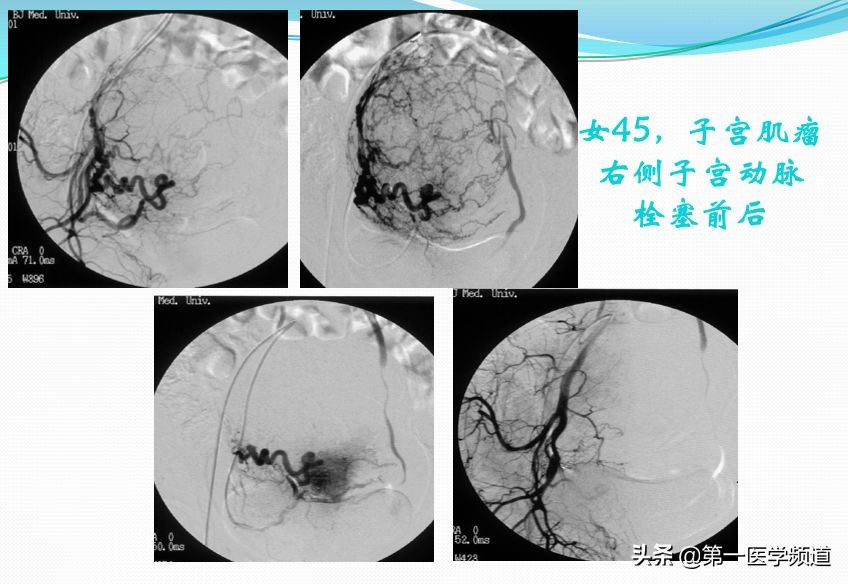

这也是一个非常典型的子宫肌瘤患者,45岁,右侧子宫动脉栓塞前后的对比图片。我们直接插管到子宫动脉以后,右侧子宫动脉做的造影,显示一个巨大的肌瘤。切除巨大的肌瘤以后,我们给她做栓塞治疗,栓塞治疗以后子宫肌瘤的动脉未见明确显示。